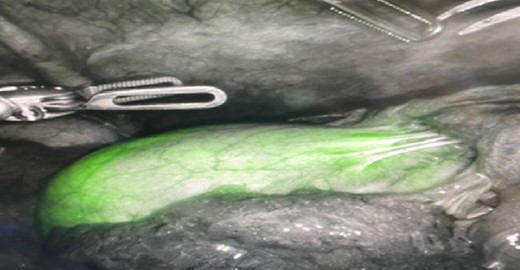

In the peri-operative period, a bolus ICG solution (2.5 mg in 10 mL of sterile saline) was administered intracystically via percutaneous cholecystostomy drain within 1 hour of the operative start time. An infra-umbilical incision was made, and a Hasson trocar was placed and insufflated with 15 mmHg of carbon dioxide. A laparoscope was inserted to inspect the abdomen. An 8 mm 30-degree laparoscope was introduced, and three additional 8 mm trocars were placed, one in the epigastrium and two in the right upper quadrants. Laparoscopic near-infrared cholangiograms were captured using the Firefly system on the DaVinci robot, as demonstrated in Figs 2 and 3A and B and 4A) with Fig. 4B displaying the gallbladder fossa after removal.

Gallbladder and cystic duct identification without (A) and with NIRF ICG (B). Arrow reflects improved cystic duct visualization.